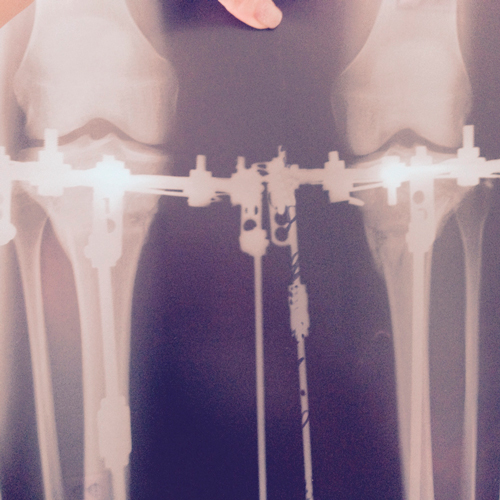

рентген в процессе исправления деформации.

SAM_0479.JPG

SAM_0478.JPG